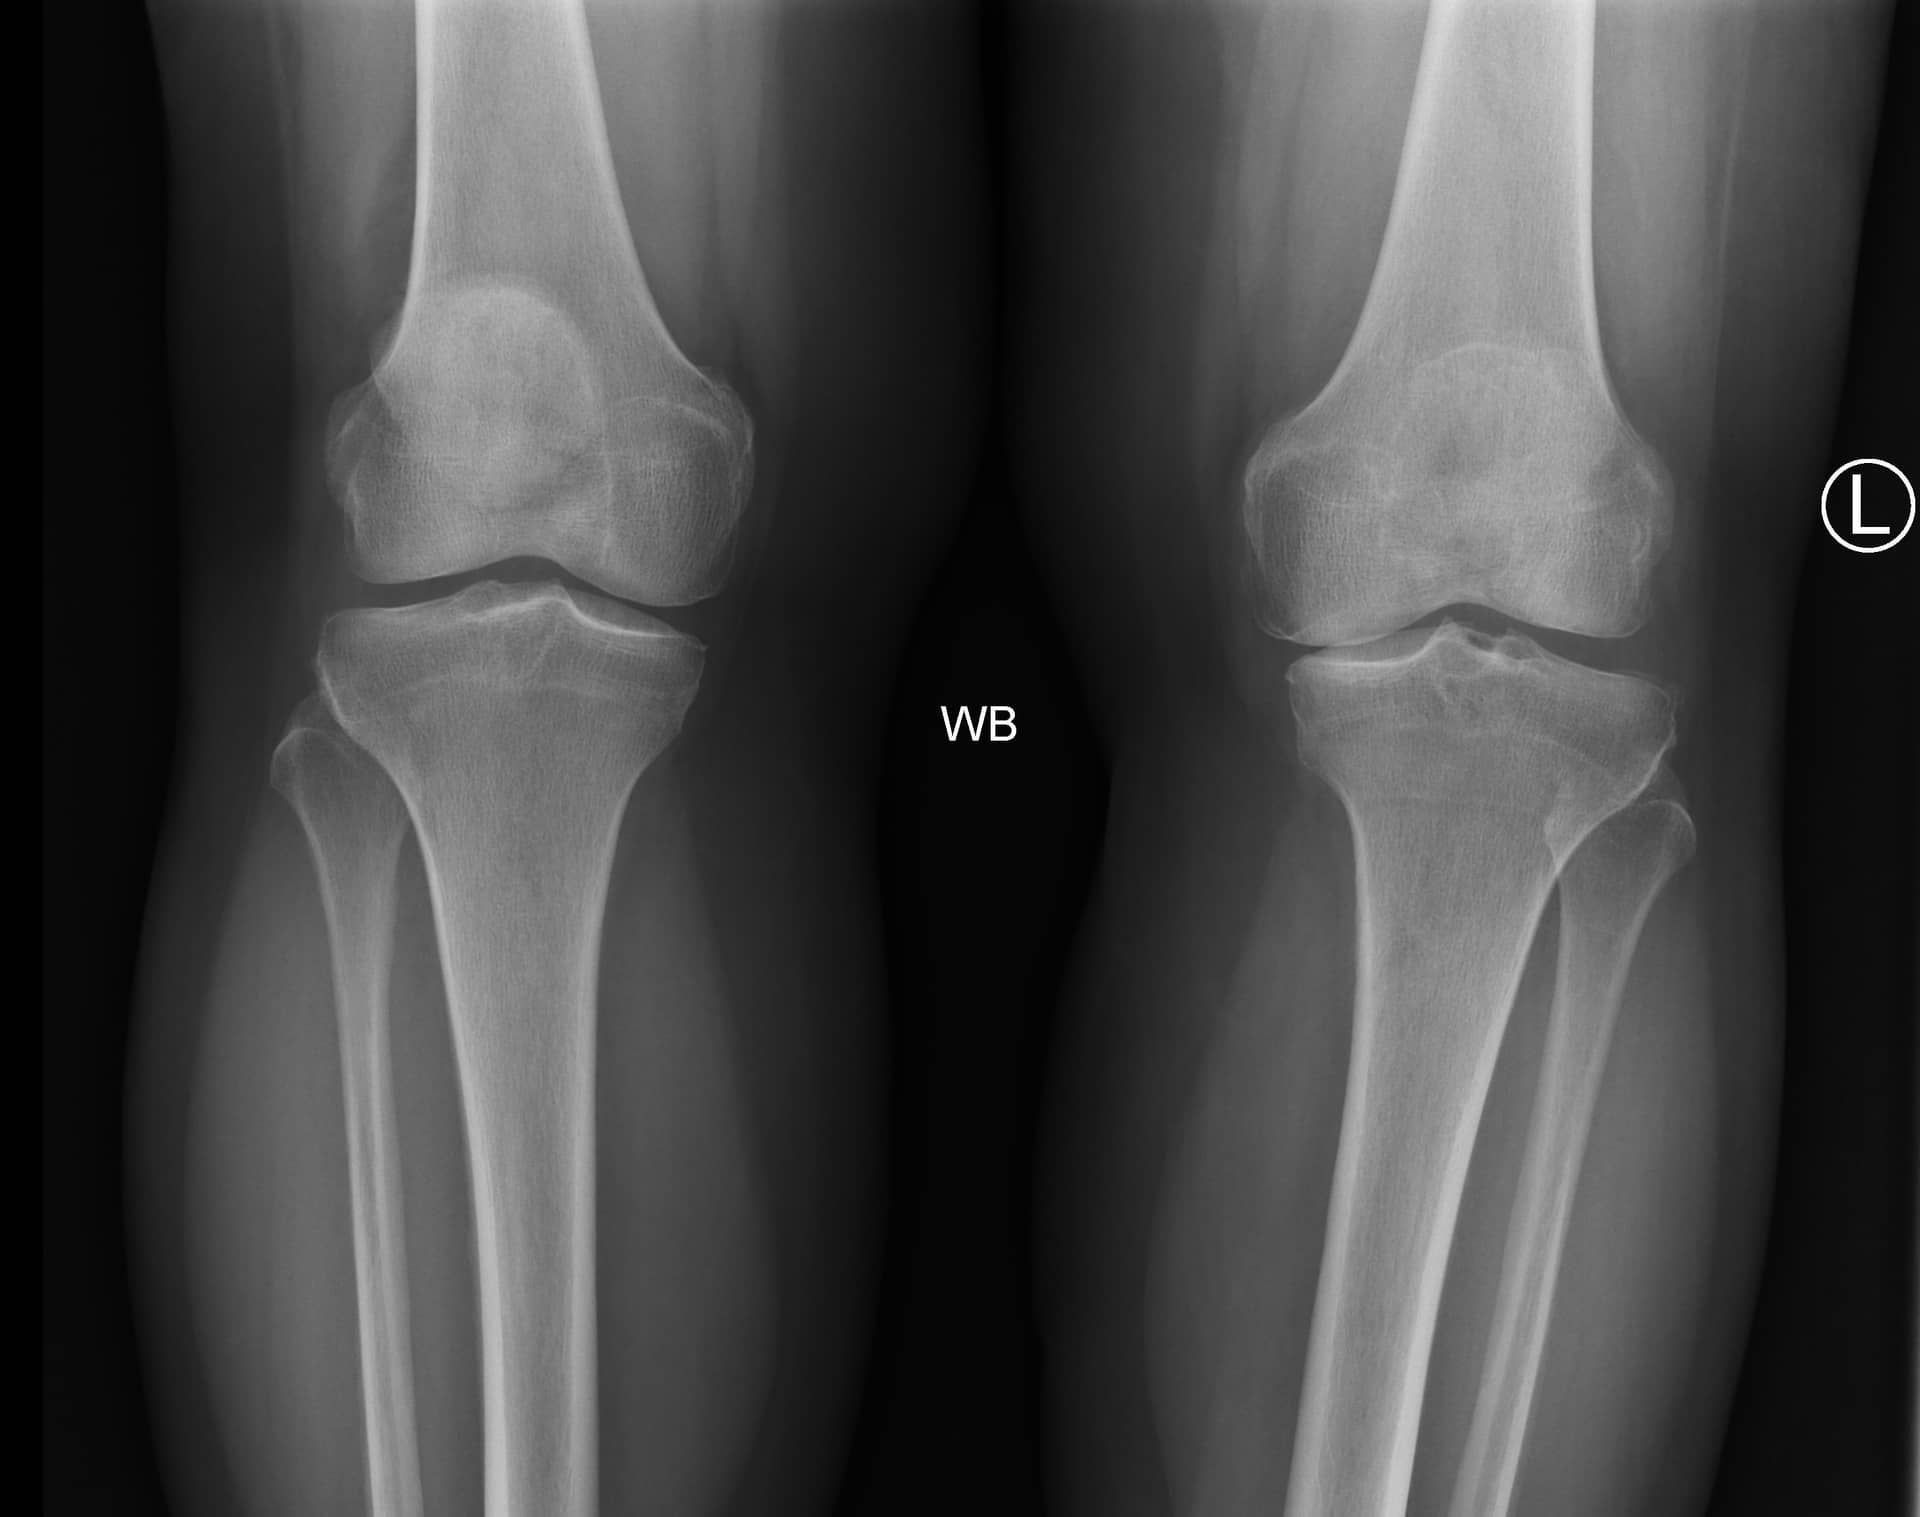

रोगी एक 66 वर्षीय महिला है जो चोट या आघात के इतिहास के बिना बाएं घुटने के दर्द के 2 साल के इतिहास के साथ प्रस्तुत करती है। दर्द लंबे समय तक अनुकरण, सीढ़ियों पर चढ़ने और लंबे समय तक खड़े रहने से बढ़ जाता है। आजमाए गए उपचारों में ब्रेसिंग, विरोधी भड़काऊ मौखिक दवाएं, अच्छी अस्थायी राहत के साथ कॉर्टिकोस्टेरॉइड इंजेक्शन और औपचारिक भौतिक चिकित्सा शामिल हैं। उसके पास उच्च रक्तचाप, हाइपरलिपिडिमिया और चिंता का पिछला चिकित्सा इतिहास है।

रोगी आरामदायक, अच्छी तरह से दिखाई देने वाला और समय, स्थान और व्यक्ति के लिए उन्मुख था। वह एक एंटाल्जिक चाल के साथ घुलमिल गई। उसके बाएं निचले छोर की जांच से पता चला कि त्वचा साफ और बरकरार थी। जांघ और पैर के डिब्बे नरम थे। उसे दर्द के बिना गति की एक सामान्य कूल्हे की सीमा थी। मोटे तौर पर, उसके घुटने हल्के वरस विकृति में थे। एक मध्यम घुटने का बहाव था। उसके घुटने की गति 0 ° से 115 ° तक फ्लेक्सन थी। उसे औसत दर्जे की संयुक्त रेखा पर कोमलता थी। उसके घुटने की लिगामेंट परीक्षा पूर्ववर्ती दराज, लाचमैन, पश्चवर्ती दराज, और वरस और वाल्गस तनाव परीक्षण के लिए स्थिर थी। उसका एक्सटेंसर तंत्र बरकरार था, और उसे सीधे पैर उठाने के साथ कोई दर्द नहीं था। वह न्यूरोवास्कुलर रूप से दूर से बरकरार थी।

कुल घुटने के आर्थ्रोप्लास्टी (टीकेए) के साथ आगे बढ़ने का निर्णय लेने से पहले महत्वपूर्ण रेडियोग्राफी में वजन-असर एपी, पीए फ्लेक्सन, पार्श्व और सूर्योदय दृश्य शामिल हैं। कुछ सर्जन लंबे पैर संरेखण रेडियोग्राफ की समीक्षा करना भी पसंद करते हैं। इस रोगी के लिए छवियों ने हड्डी-पर-हड्डी संपर्क, सबकॉन्ड्रल स्केलेरोसिस और मल्टीपल पेरिआर्टिकुलर ओस्टियोफाइट्स के साथ मेडियल और पेटेलोफेमोरल डिब्बे में संयुक्त स्थान के नुकसान के साथ गंभीर अपक्षयी परिवर्तनों का खुलासा किया। हल्के वरस यांत्रिक संरेखण था। पटेला सूर्योदय के दृश्य पर केंद्रीय रूप से ट्रैक कर रहा था।